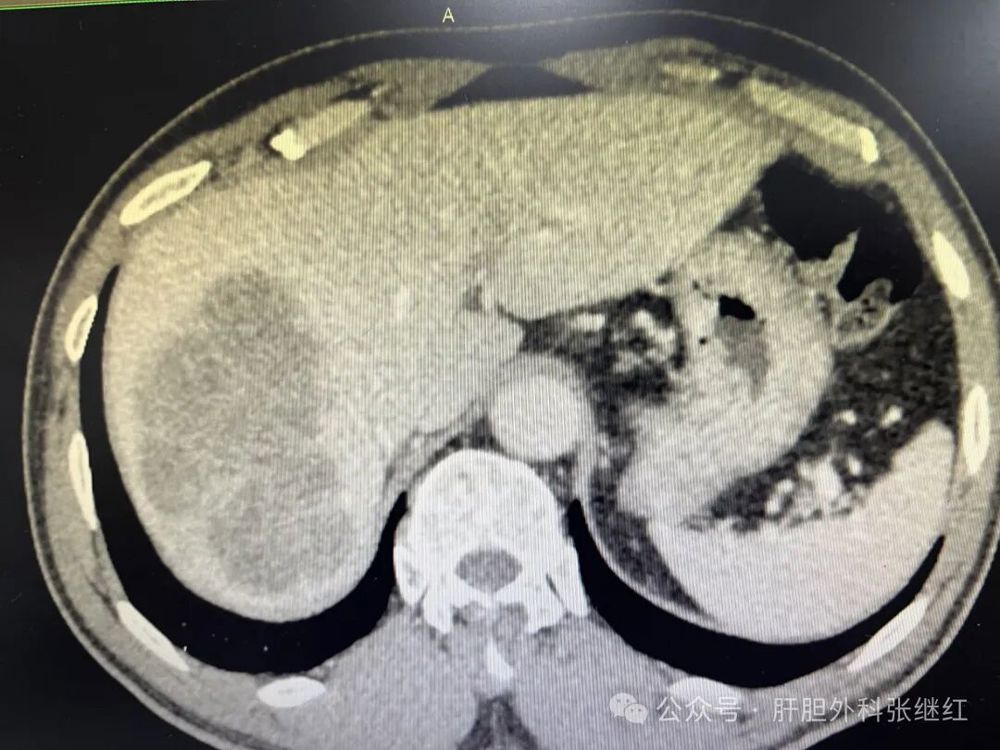

靶向免疫治疗3个疗程后CT